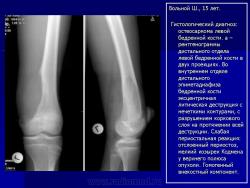

Первым исследованием, на основании которого обычно ставится диагноз остеогенной саркомы, является рентгенодиагностика. Это исследование позволяет заподозрить наличие остеосаркомы у пациента, а также выявляет наличие мягкотканного компонента, патологического перелома, определяет размеры опухоли, и оптимальный уровень проведения биопсии.